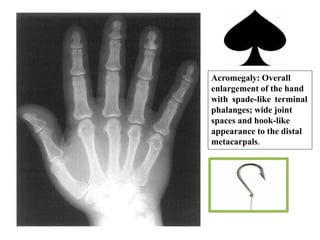

Appendicular Skeleton:

• Hands show characteristics enlargement of bones &

soft tissue with spade like appearance of terminal tufts

or arrow head distal phalanges.

• Widening of the joint spaces (overgrowth of

articular cartilage).

Acromegaly: Overall

enlargement of the hand

with spade-like terminal

phalanges; wide joint

spaces and hook-like

appearance to the distal

metacarpals.